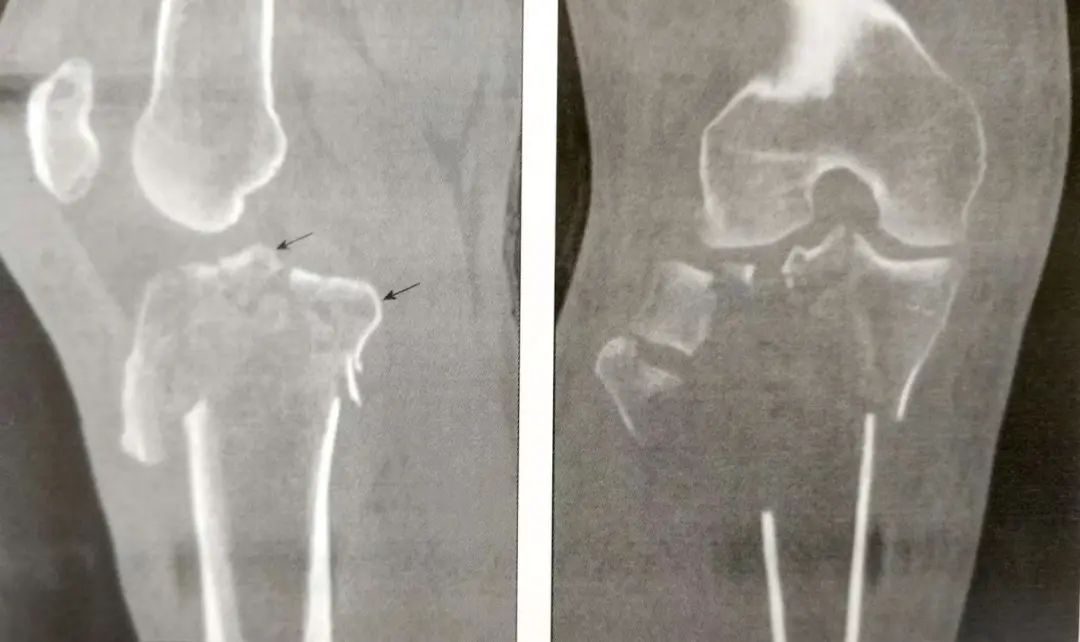

CT扫描能有效观察关节内骨折情况。标准的扫描应该包括轴位、冠状位和矢状位;

CT可以提供完整的关节损伤信息,包括髁间嵴骨折,关节面塌陷的位置和程度,骨折块的大小,前交叉韧带撕脱骨折和后交叉韧带胫骨附着点撕脱骨折。

▲髁间嵴骨折

▲关节面塌陷的位置和程度

A:前交叉韧带撕脱骨折(箭头)

B:后交叉韧带胫骨附着点撕脱骨折

它们帮助确定骨折的切口。如一个前外侧髁间嵴骨折,需要采用膝关节外侧入路。

▲前外侧髁间嵴骨折(箭头)